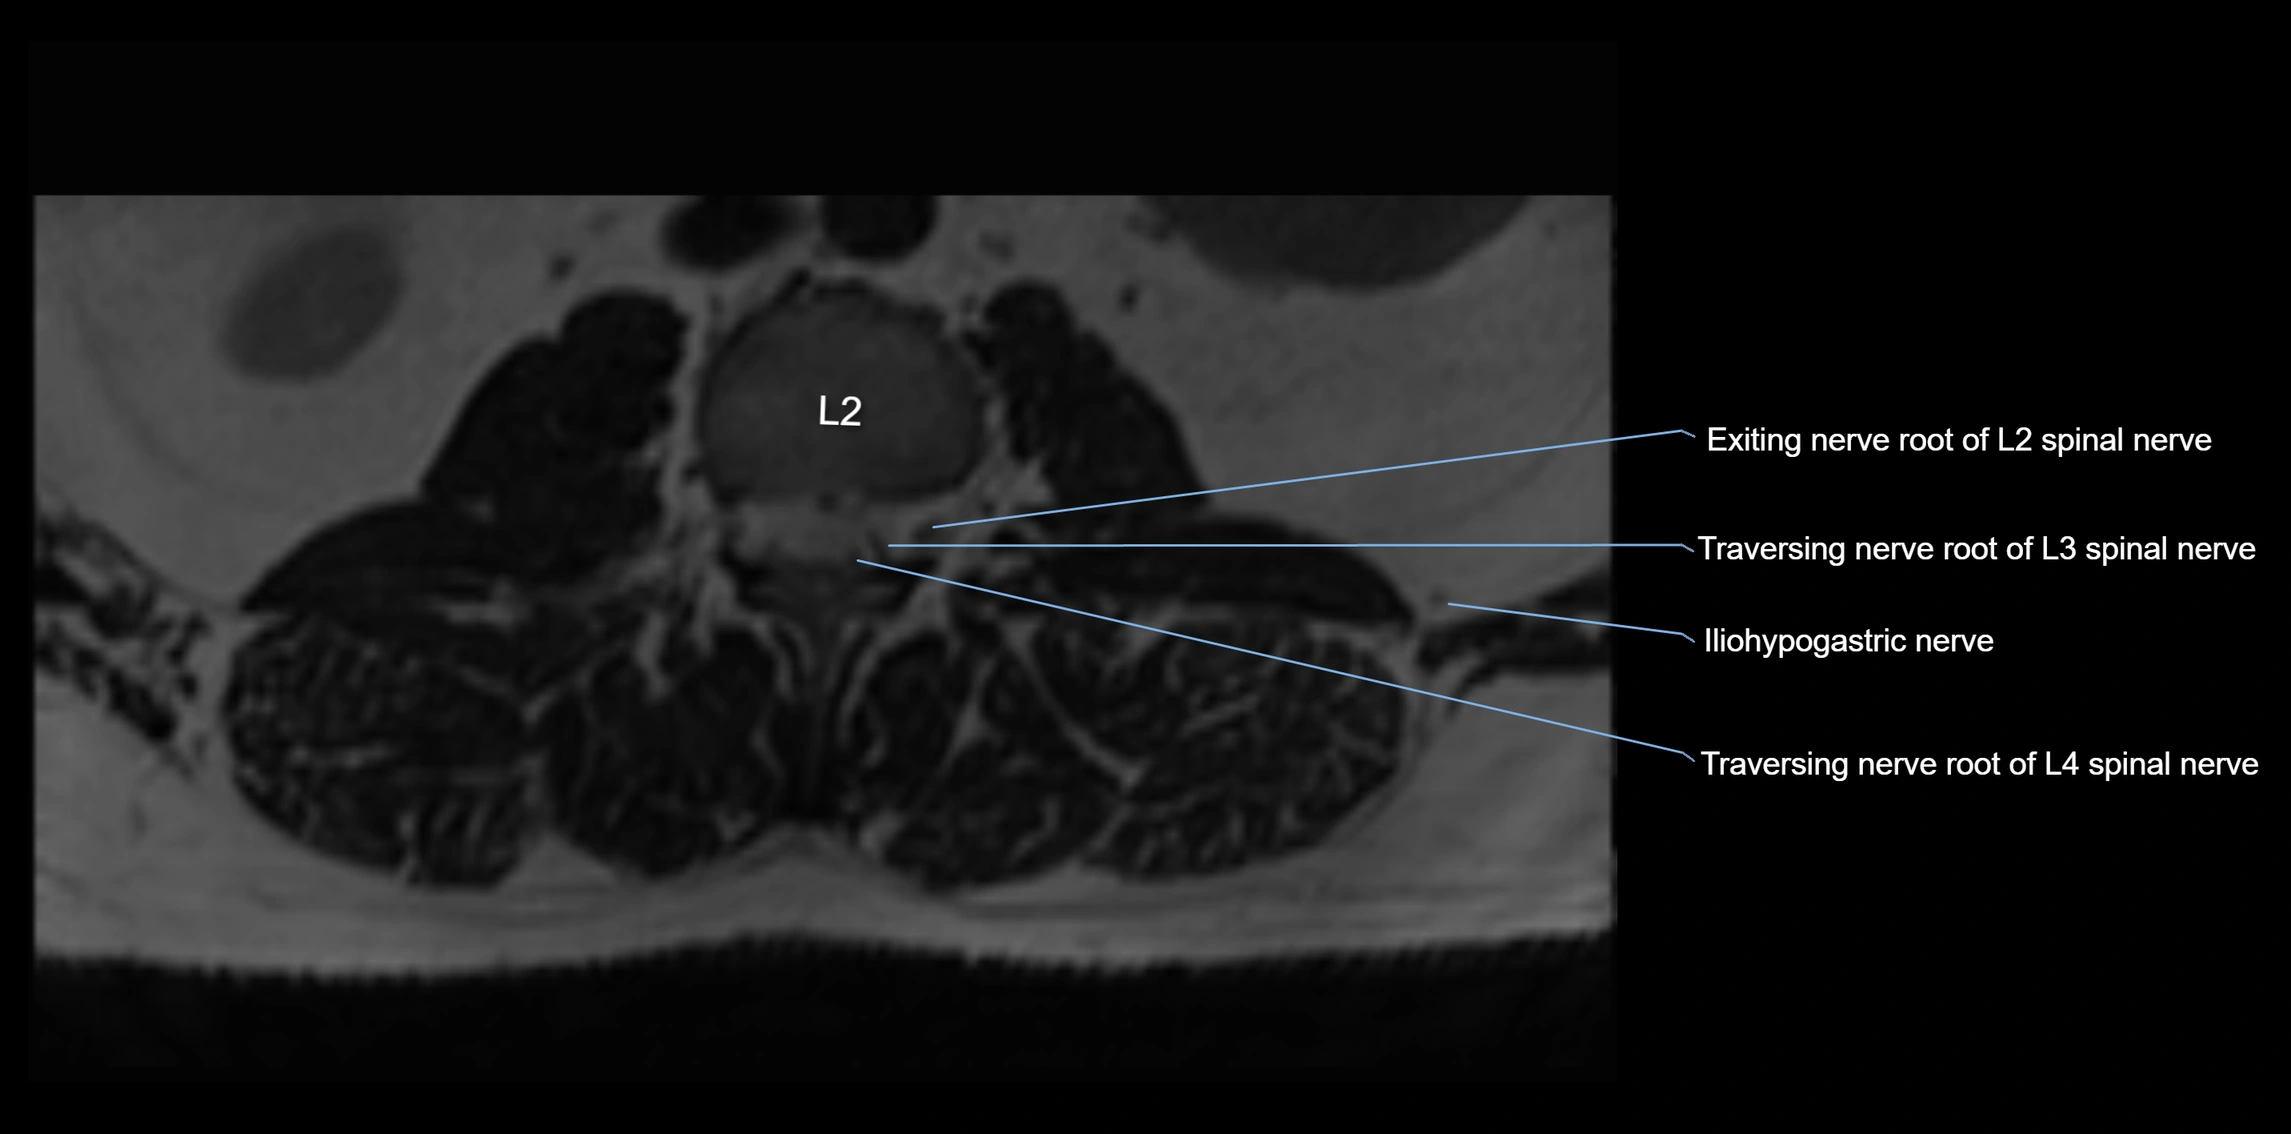

MRI image

image